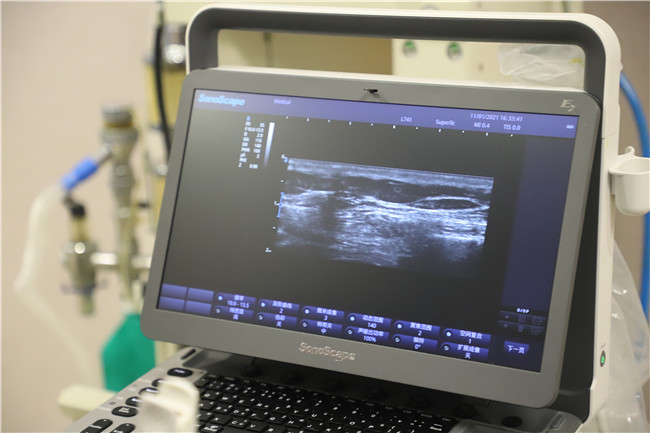

辗转回到当地后,在家人的陪同下,经过多方打听,潘老太来到了丹江口市第一医院疼痛科门诊,在详细了解了患者的情况后,综合考虑各种因素,疼痛科伍医生采用了“超声引导下胸壁神经阻滞带状疱疹神经痛治疗技术”为她治疗,经过几个疗程的治疗,疗效显著,疼痛明显缓解。

“带状疱疹是由水痘-带状疱疹病毒引起的感染性皮肤病,而在带状疱疹急性期,如果没有接受有效镇痛治疗阻断疼痛途径,患者会在疱疹好转后仍遗留明显神经痛,可严重影响患者日常生活、情绪和睡眠,疼痛程度较重、持续时间较长者可导致精神焦虑、抑郁等表现。” 伍医生介绍,针对这类患者,超声引导神经阻滞治疗是一种有效的治疗手段。它是通过超声引导实施精准定位神经阻滞,采用超声精确定位、靶点注射,能避免药物误入血管或穿刺过程损伤神经,更精准、有效解除疼痛,提高患者生活质量。